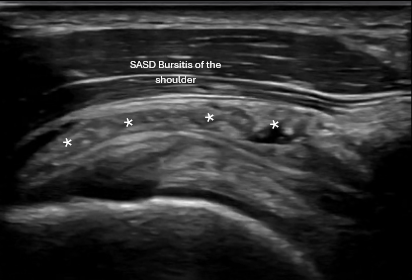

Dynamic shoulder ultrasound exam showing acute bursitis with rotator cuff tear in active adult

Other common shoulder findings

• Subacromial bursitis

Ultrasound allows us to see the injury directly, assess it dynamically, and compare to the opposite side when needed

Musculoskeletal ultrasound image showing rotator cuff tendon injury